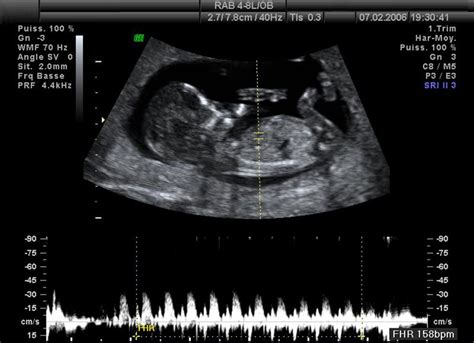

- Ultrazvukové vyšetrenie: Toto vyšetrenie je najdôležitejším diagnostickým nástrojom. Odhalí abnormálny typ maternice a často aj chýbanie plodu. Ultrazvukový obraz pri kompletnej mole je charakteristický odrazmi mnohopočetných priehradok, ktoré sa označujú ako „snežná búrka“ alebo „snehová víchrica“, pretože na monitore naozaj vyzerajú ako husté sneženie. Typické je tiež zobrazenie mnohopočetných luteinných cýst na vaječníkoch.